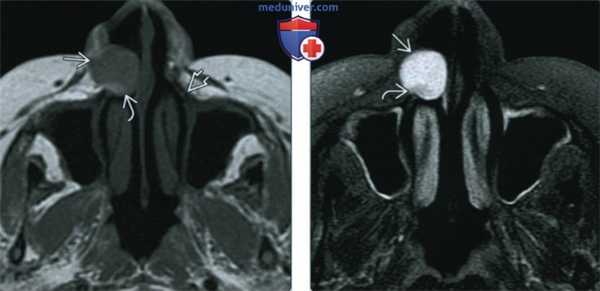

(Слева) При аксиальной МРТ Т1ВИ С+ FS в левой височной мышце визуализируется венозная мальформация, умеренно накапливающая контраст; в левой гемисфере мозжечка определяется врожденная венозная аномалия, в области моста мозга также визуализируется вероятная венозная аномалия меньшего размера или телеангиэктазия.

(Справа) При аксиальной МРТ Т1ВИ С+ FS в левой височной ямке визуализируется венозная мальформация, неравномерно накапливающая контраст.

(Слева) При аксиальной МРТ STIR в подкожных тканях в области верхней губы определяется венозная мальформация в виде объемного образования с бугристыми краями, хорошо отграниченного от окружающих тканей. Патологические изменения со стороны костей и зубов отсутствуют.

(Справа) При аксиальной МРТ Т1ВИ С+ FS y этого же пациента визуализируются патологически расширенные венозные сосуды, умеренно и неравномерно накапливающие контраст.